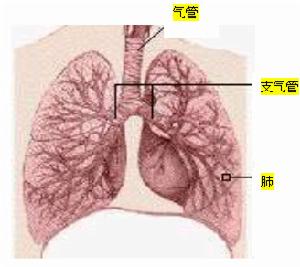

| 研究範圍及進展呼吸內科是研究呼吸系統疾病的學科。它是既古老又年輕的學科,說它古老是因為,自從人類認識疾病以來,呼吸系統疾病就一直是危害人類健康的常見病和多發病,八十年代中期的統計資料表明,呼吸系統疾病仍然是導致死亡的主要疾病。在死亡的順序上排列第二。現在我們來認識一下這些可怕的疾病吧? |